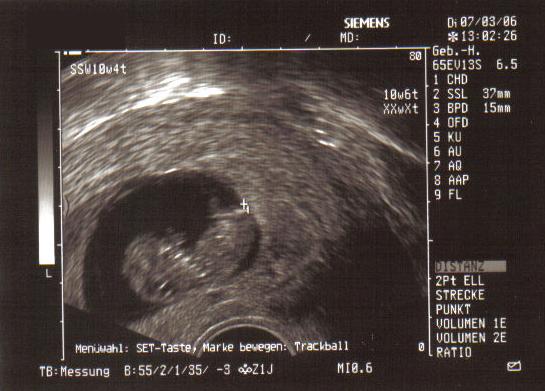

Mein Wurm Ende 11. Woche:

Bilder

• 11.Woche.jpg

37,59 kB, 545×391, 234 mal angesehen